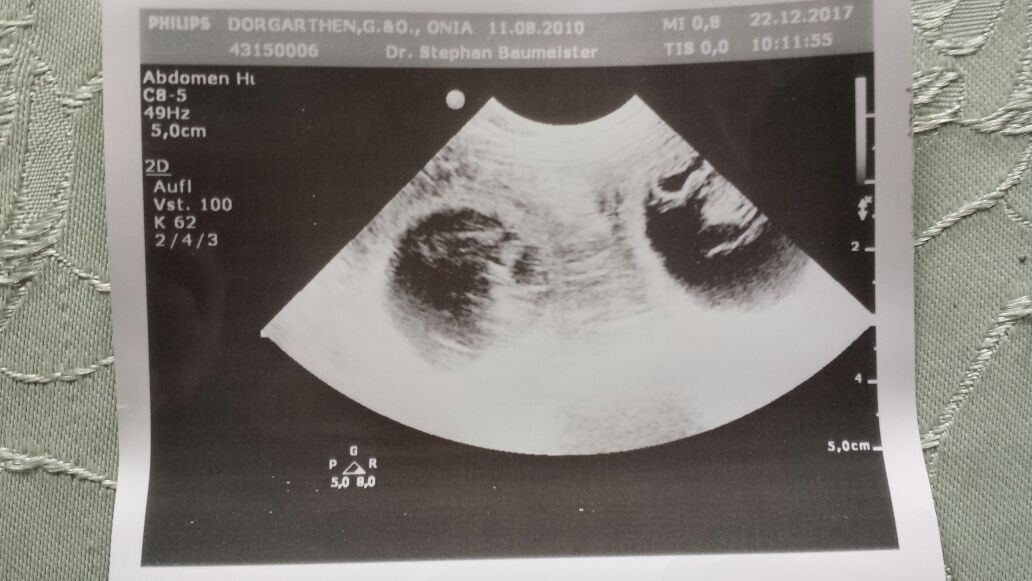

Hurra, wir haben heute schon unser Weihnachtsgeschenk erhalten. Onia bekommt Welpen. Per Ultraschall konnten wir einige schöne Fruchtanlagen sehen. Ansonsten geht es ihr gut und sie zeigt die typischen Trächtigkeitsbegleiterscheinungen wie Futterunlust ... Leckereien gehen immer und noch schmusiger als bisher .. wenn es da noch eine Steigerung gibt. Nur im Gelände merkt man ihr nichts an, da ist sie noch spritzig und temperamenttvoll wie eh und je. Wir hoffen die zweite Trächtigkeitszeit geht genau so unproblematisch weiter.

Hier das erste Foto von den X-chen: